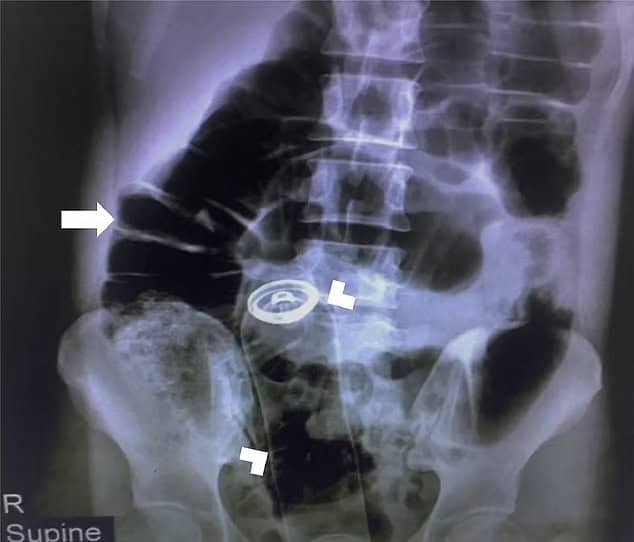

وكتب الفريق الطبي في المجلة المرئية لطب الطوارئ، أن المسعفين لم يتمكنوا أيضًا من العثور على “أي جزء من العلبة” ظاهراً من خلال فتحة الشرج، ما يعني أنها دخلت إلى المستقيم.

ووفقاً لما كتبه الأطباء، فقد كان الشاب يعاني من ألم شديد لدرجة أنه لم يتمكن من الخضوع لفحص المستقيم، مما أجبر المسعفين على الاعتماد على الأشعة السينية للعثور على المكان الذي ذهبت إليه العلبة.